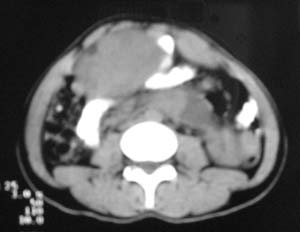

以下是引用zjzjr在2007-9-27 22:20:00的发言:[br]肠腔受推移,未见明显扩张及液平,所以考虑是肠外病灶, 间叶源性肿瘤?脂肪瘤?建议增强。

以下是引用guzhongliangddd在2007-9-27 23:21:00的发言:[br][br]与肠内高密度相同,病灶应该没有钙化,我认为首先考虑是间叶组织的良性肿瘤。建议楼主做后重建观察。中线区域大血管旁未见确切增大淋巴结。病灶对肠道只是推移关系。

以下是引用余辉在2007-9-27 22:24:00的发言:[br]暂考虑肠道间质来源肿瘤如小肠平滑肌肉瘤/瘤可能,应该增强